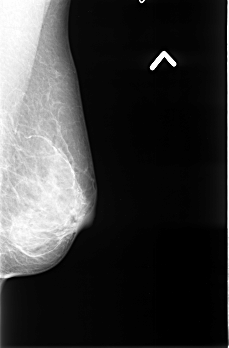

B_3396_1.RIGHT_MLO

RIGHT_MLO LINES 4528 PIXELS_PER_LINE 2960 BITS_PER_PIXEL 12 RESOLUTION 50 OVERLAY